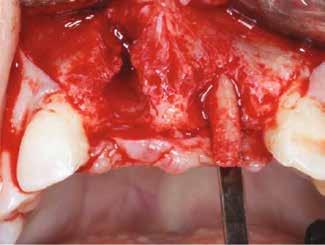

Egy 47 éves páciens jelentkezett nálunk egy alsó, hátsó foghiánnyal, ahol jelentős csontfelszívódást tapasztaltunk a moláris fogak korábbi eltávolítása miatt (1. ábra). Két implantátum körül is volt ínyrecesszió, illetve a keratinizált íny mennyisége minimális volt (kevesebb, mint 1 mm). 4 hónappal az implantációt követően ínykorrekciót végeztünk.

horizontális metszéssel kötöttük össze (2–5. ábra). A metszések hosszát és a köztük lévő távolságot minden esetben a lágyszövet augmentációhoz szükséges keratinizált szövet határozza meg. A lebeny deepitelizációját egy 15C-s szikepengével végeztük (6. ábra). Ezt követően félvastag lebenyt preparáltunk (7. ábra). A lebenyt apikálisan, az alapjáról belső, felületes metszéssel felszabadítottuk, hogy passzívan áthelyezhessük és rögzíthessük, feszülés nélkül. Meziális irányba 180 fokkal átforgattuk (8–9. ábra). A meziális papillát alagúttechnikával (tunnelling technique) készítettük elő a graft befogadására (10. ábra). Az így kialakított lebenyt a recipiens ágyban rögzítettük az újonnan kialakított vesztibulum alapjánál 5-0 nem felszívódó PTFE (Coreflon, IMPLACORE) varratokkal. A graftot behajtottuk az ínyszél alá és meziális oldalon rögzítettük PTFE varratokkal (11–14. ábra) A műtétet követően napi kétszeri, 0,12%-os klórhexidin tartalmú szájvízzel történő öblögetést javasoltunk a páciensnek, két héten keresztül. Gyulladáscsökkentésre 8 óránként 400 mg Ibuprofént javasoltunk, három napon keresztül. A páciens elmondása szerint sem fájdalmat, sem különösebb diszkomfortot nem tapasztalt. Ezt követően, további 4 héten keresztül, 0,2%-os klórhexidin tartalmú szájvízzel történő öblögetést javasoltunk a betegnek és instruáltuk, hogy lehetőleg ne mossa fogkefével az érintett területet. A varratokat egy héttel később távolítottuk el. A donor és a recipiens terület – 10 nappal a műtétet követően – kiválóan gyógyult (15–16. ábra). Az ezt követő kontrollokat a következő időpontokban ejtettük meg: kettő, illetve négy héttel a műtét után, majd három, hat és tizenkét hónappal később, ezt követően pedig félévente (17–20. ábra). Minden kontroll alkalmával professzionális fenntartó kezelést végeztünk a területen.

ságát egy ISO #15-ös endodonciai fájllal mértük 2 mm-re a marginális ínyszéltől meziálisan, disztálisan, illetve az implantátum tengelyében (mint referenciapont). A keratinizált íny szélességét parodontológiai szondával regisztráltuk a kiindulás és a kontrollvizsgálatok alatt. A méréseket elvégeztük a műtét előtt, közvetlenül utána, 4 héttel később, majd egy és két év elteltével. A klinikai paramétereket (keratinizált íny szélessége, lágyszövet volumen és recessziófedés) regisztráltunk a kiinduláskor és az utánkövetés időpontjai alatt. Kiinduláskor a feszes íny szélessége minimális volt (1 mm). A keratinizált ínyszélesség terén négy hétnél 2 mm-t sikerült nyerni, egy évnél 3 mm-t és öt év alatt 5 mm-t. A recessziót 100%-osan sikerült fedni 4 hét után, és ez nem változott sem egy év, sem öt év után.